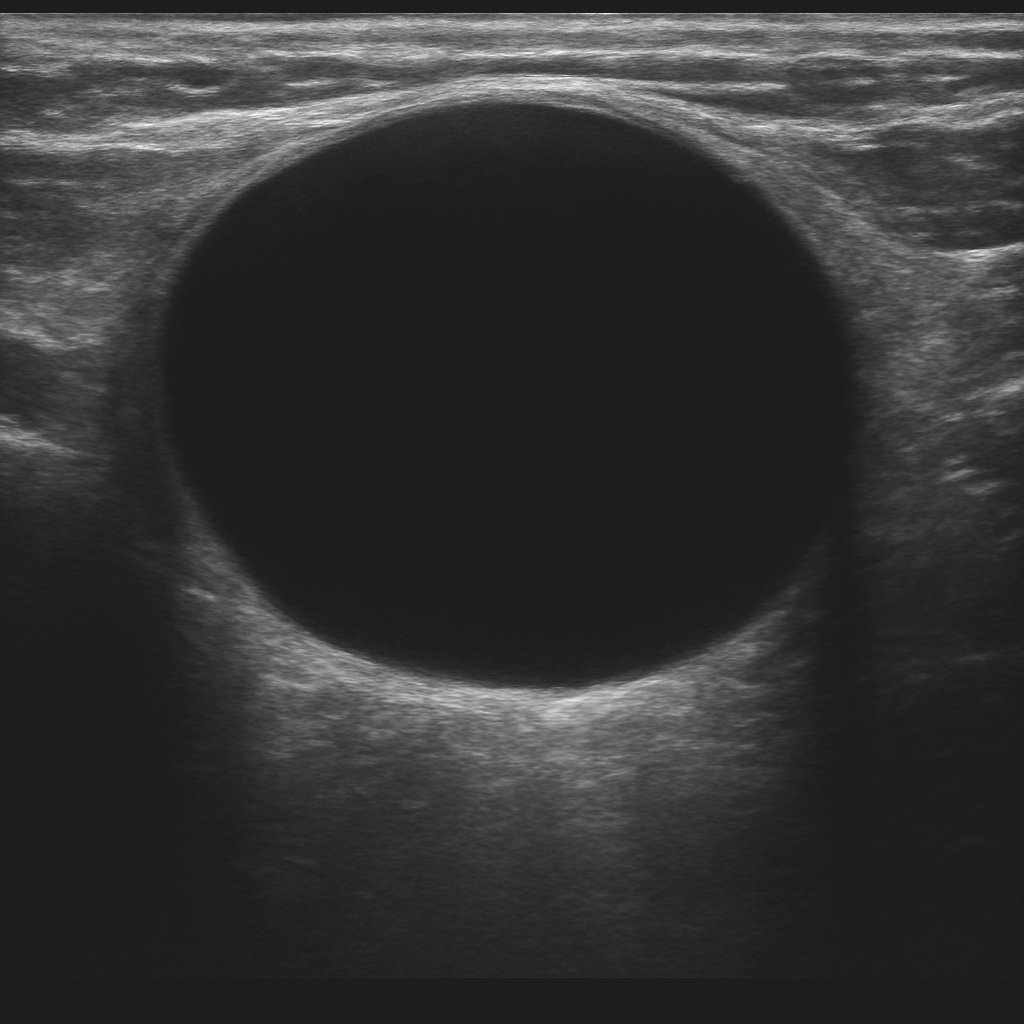

Traitement des Kystes Thyroïdiens : Évacuation et Alcoolisation

Une solution efficace pour les kystes symptomatiques

Les nodules kystiques représentent 3 à 10% des nodules thyroïdiens. L'évacuation suivie d'alcoolisation (PEI - Percutaneous Ethanol Injection) constitue une alternative mini-invasive à la chirurgie pour ces lésions spécifiques.

Indication thérapeutique ciblée

L'intervention est proposée pour les kystes thyroïdiens :

- Volumineux et gênants (compression, inconfort, impact esthétique)

- Récidivants après simple évacuation

- Nécessitant une confirmation de leur nature bénigne (parois épaissies)